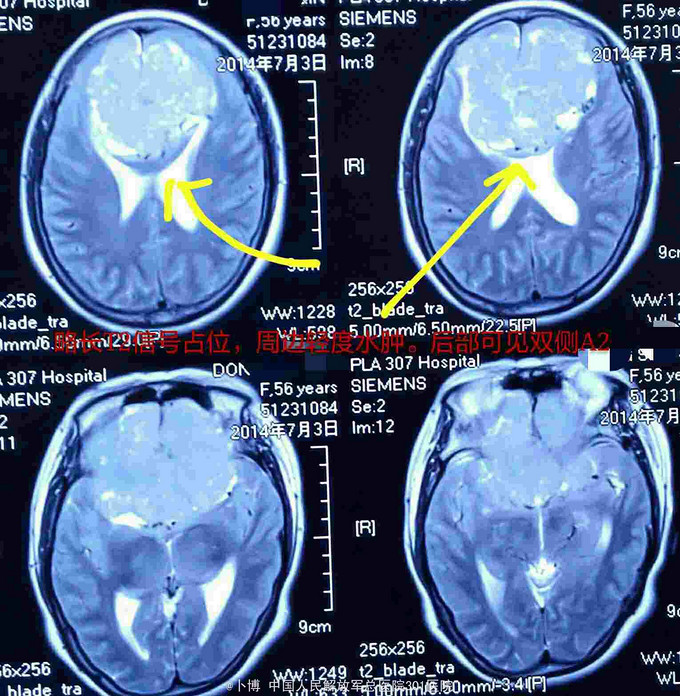

前颅窝底占位:脑膜瘤

脑膜瘤

前颅窝底占位:脑膜瘤。 手术入路:冠状切口,双侧额下入路肿瘤切除。

术后一年。复查MR示肿瘤全切。